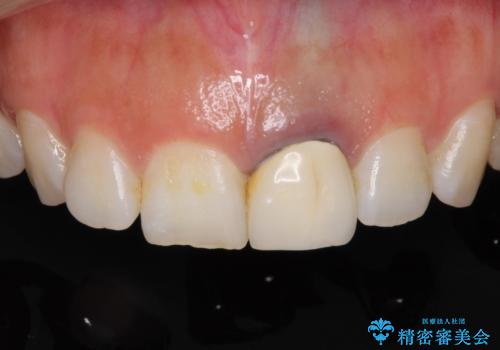

- 前歯をメタルの被せものにしており、セラミックに変えるのを希望された患者様です。

土台も金属だったため、歯がかなり黒く変色していました。

色は完全にとるのが不可能であることをご了承頂いた上で、土台と被せものの治療を行いました。

今回は歯自体が黒くなって歯茎から透けて見えている黒ずみのため、セラミック治療で改善させることは困難だというお話をしました。その上でできる範囲できれいに治療することになりました。